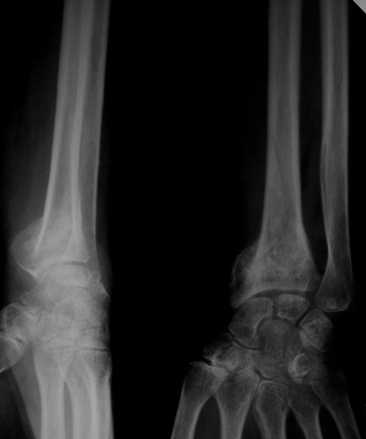

Обратилась женщина, 55 лет. Травма 3 месяца назад, лечилась по месту жительства (Рис.1). Косорукость, боли, ограничение движений. Досняли - рис.2-6. Хотелось-бы услышать мнения  об объеме операции.